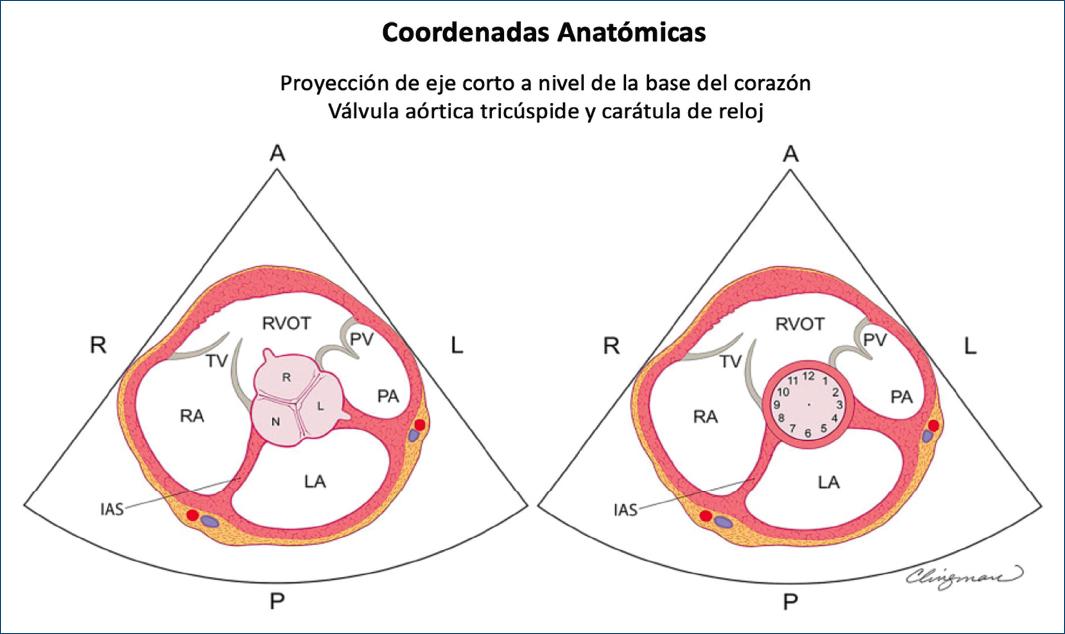

Figura 5 Esquema basado en ecocardiografía transtorácica en eje corto, puntos de referencia anatómicos de la base del corazón y esfera del reloj para el diagnóstico y fenotipado de la aorta bicúspide. Panel izquierdo: esquema de la válvula aórtica tricúspide normal en la vista ecocardiográfica paraesternal de eje corto, aplicable a vistas similares obtenidas con tomografía computarizada cardiaca y resonancia magnética cardiaca. La cúspide coronaria derecha (R pequeña) es anterior y se coloca entre las inserciones de la válvula tricúspide (TV) y la válvula pulmonar (PV). La cúspide coronaria izquierda (L pequeña) es postero-lateral y está relacionada con la aurícula izquierda (LA), mientras que la cúspide no coronaria (N pequeña) es la más posterior y está relacionada con el septum interauricular (IAS). Nótese el origen de las arterias coronarias en las cúspides derecha e izquierda. Estas referencias anatómicas de cada cúspide en relación con las estructuras adyacentes son críticas para determinar qué dos cúspides están fusionadas. Panel derecho: la circunferencia anular de la válvula aórtica se puede visualizar como la cara de un reloj. Las válvulas bicúspides fusionadas con fusión de la cúspide derecha-izquierda generalmente tienen comisuras a las 4 y 10 o 5 y 11 en punto (Figs. 6 y 7), y la anatomía relativa a las estructuras adyacentes sugiere fusión de la cúspide derecha-izquierda. En la fusión cúspide derecha-no coronaria, las comisuras suelen ser a la 1 y 7 o a las 12 y a las 6 en punto (Figs. 6 y 7); la anatomía relativa a las estructuras adyacentes sugiere fusión derecha-no coronaria. La fusión de la cúspide izquierda-no coronaria, generalmente a las 2 y 8 o 9 y 3 en punto (Figs. 6 y 7) y la anatomía relativa a las estructuras adyacentes sugieren la no fusión izquierda. Es importante tener en cuenta que puede haber superposición entre las posiciones del reloj; por lo tanto, es fundamental conocer las referencias anatómicas de cada cúspide. La identificación del rafé puede ser invaluable para determinar la cúspide unida. La identificación del origen de las arterias coronarias izquierda y derecha (panel izquierdo) también puede ser invaluable (modificada de Michelena et al., 20206 con permiso de Elsevier). R mayúscula: lado derecho del paciente; L mayúscula: lado izquierdo del paciente; P: aspecto posterior del corazón; RA: aurícula derecha; LA: aurícula izquierda; TV: válvula tricúspide; RVOT: tracto de salida del ventrículo derecho; PV: válvula pulmonar; PA: arteria pulmonar.